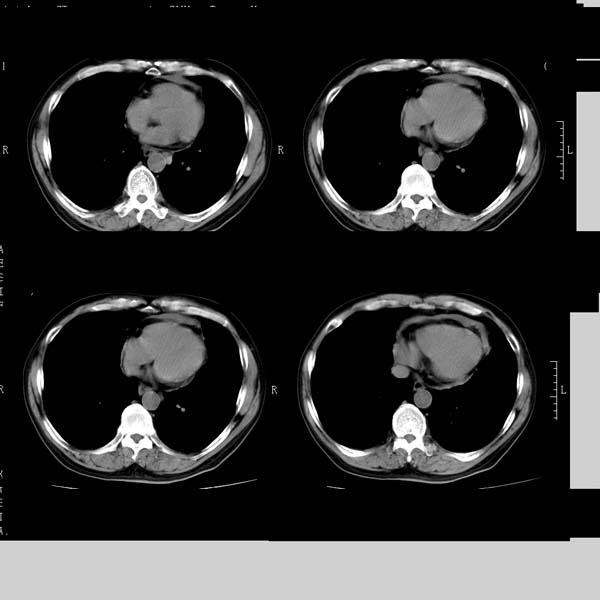

以下是引用守望可可西里在2008-6-24 1:11:00的发言:[br][br] 考虑为周围型肺癌:[br] 1.分叶结节,形态极不规则,蟹足样伸展的恶性浸润特征比较明确。[br] 2.磨玻璃影中由多个更高密度小结节聚集呈梅花瓣样。[br] 3.局部胸膜凹陷征比较明确。[br][br] 另:纵隔胸膜明显增厚、粘连。

以下是引用zjzjr在2008-6-24 11:19:00的发言:[br]支持左下肺周围型肺癌伴右肺转移,纵隔淋巴结转移,心包积液.

以下是引用zhangling在2008-6-24 14:56:00的发言:[br]我们科室意见报告为[br][br]1考虑左下肺周围型肺癌[br]2右肺小结节考虑转移瘤,纵隔淋巴结转移[br]3心包积液. [br] 各位老师分析的相当好 谢意[br]